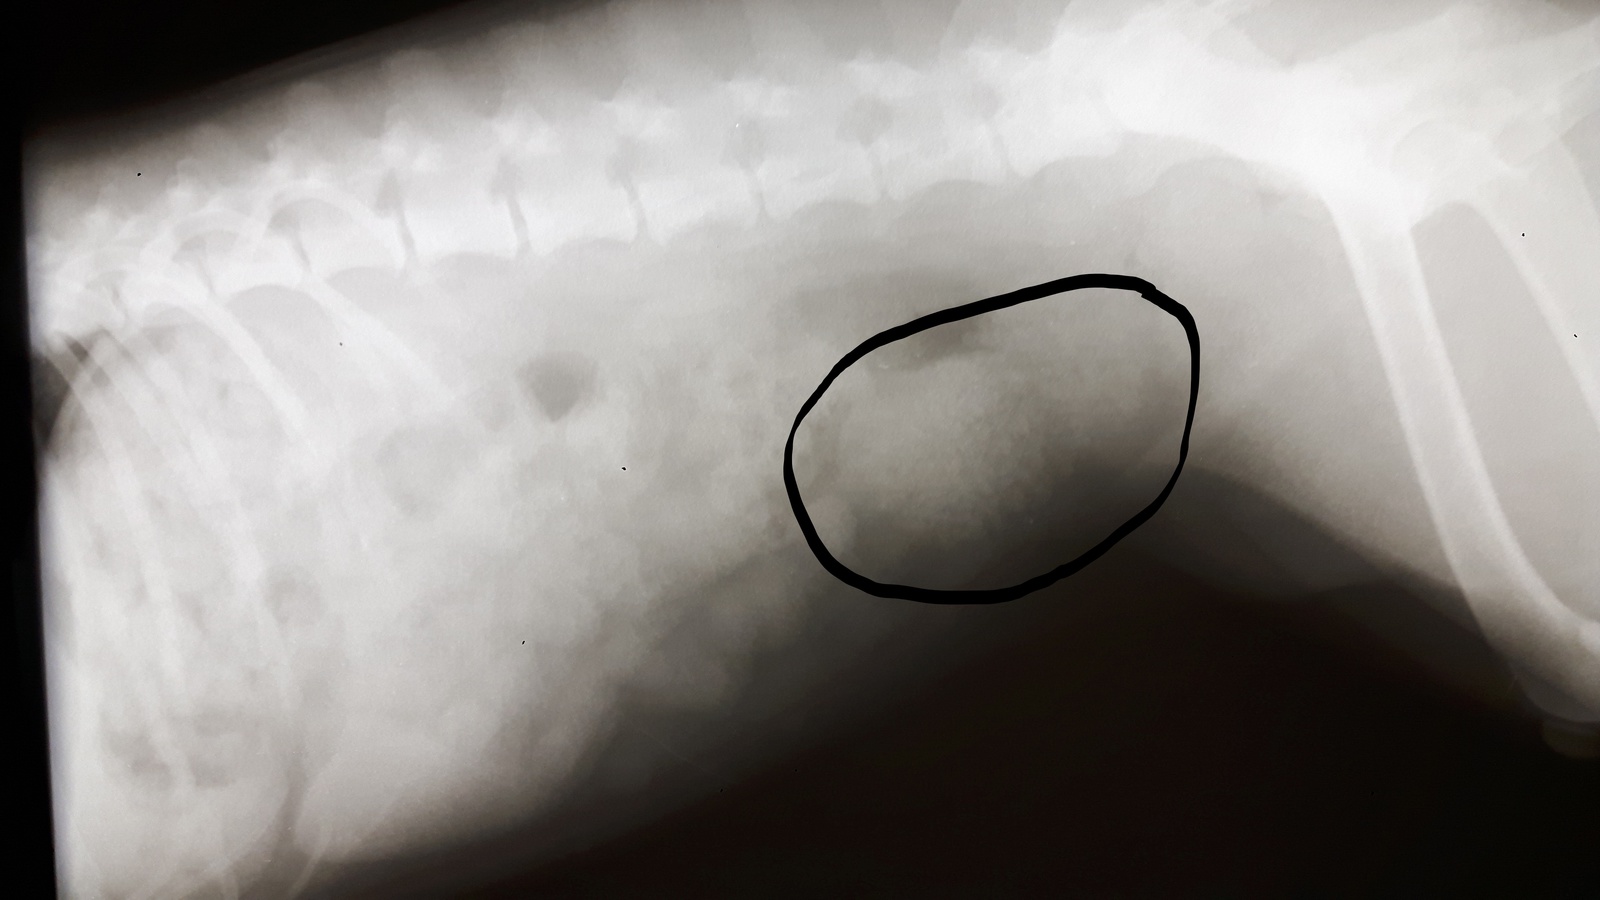

Stejný den jsme ještě provedli RTG vyšetření močového měchýře, který byl plný drobných urolitů opacity měkké tkáně, což společně s USG vyšetřením a vyšetřením moči ukazovalo s velkou mírou pravděpodobnosti na struvitovou cystolithiázu.

InkedRTG MM před operací 2_LI.jpgInkedRTG MM před operací 1_LI.jpg